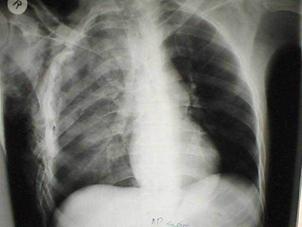

TRAUMATISME TORACICE

Pneumotorace sufocant bilateral Pneumotorace sufocant stang

Pneumotorace

sufocant stang Pneumotorace

sufocant drept Pneumotorace

sufocant drept

Imagine

CT Imagine CT